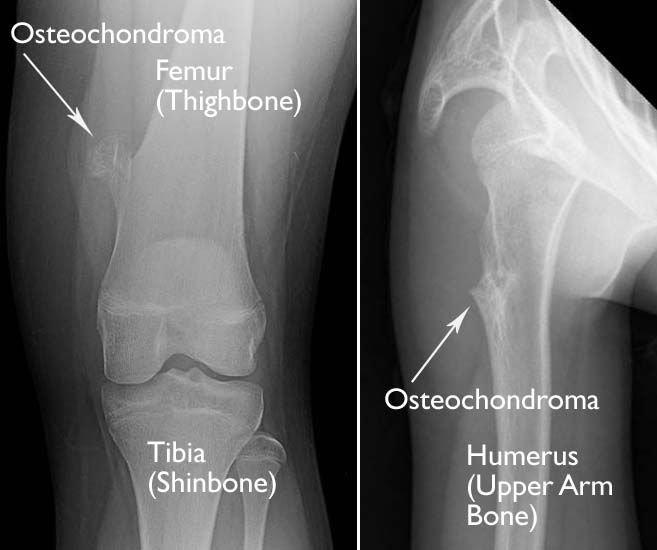

(Left) This X-ray taken of the front of the knee shows a typical pedunculated osteochondroma on the femur. (Right) This X-ray of the shoulder taken from the side shows a sessile osteochondroma on the humerus.

As a child grows, a solitary osteochondroma may develop if bone grows out from the growth plate instead of in line with it. Solitary osteochondromas are commonly found at the end of long bones where they meet to form joints, such as the knee, hip, and shoulder.

This bone outgrowth may have a stalk or stem that sticks out from the normal bone.

• If the tumor has a stalk, the structure is called pedunculated.

• If the tumor outgrowth is attached to the bone with a broader base, it is called sessile.